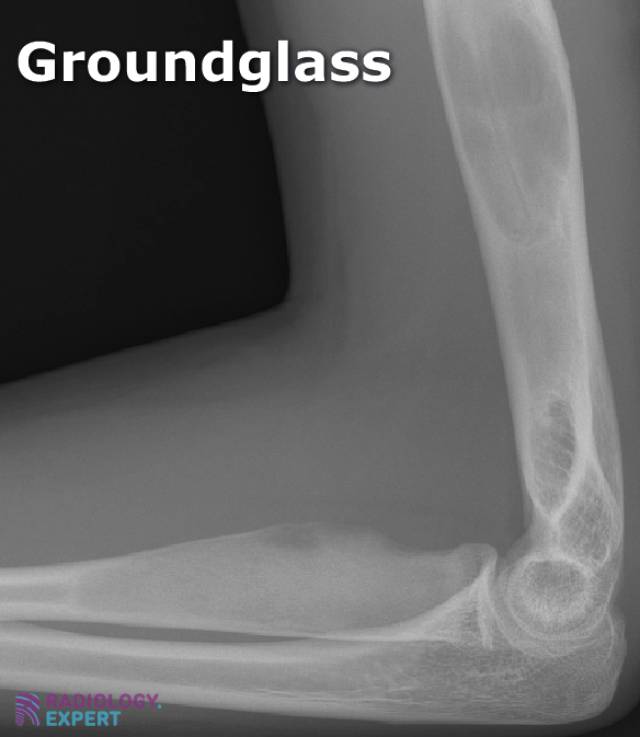

From www.radiology.expert

Bone tumours Ground Glass Appearance X Ray Dental The presence of important characteristics, such as margination, a perilesional halo, bone expansion, and growth. Ground Glass Appearance X Ray Dental.